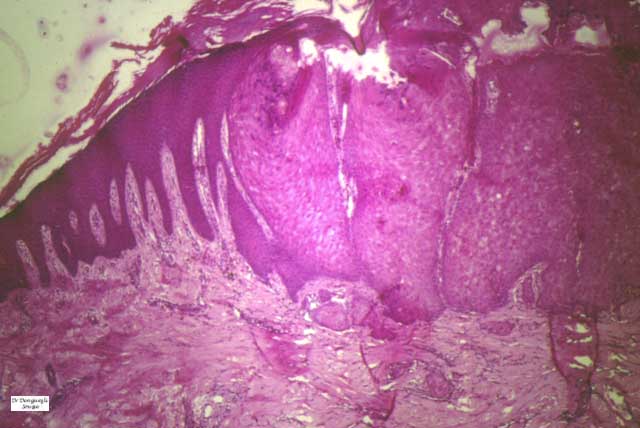

The alterations in the second stage consist of acanthosis, irregular papillomatosis, and hyperkeratosis. Intraepidermal keratinization, consisting of whorls of keratinocytes and of scattered dyskeratotic cells, is often more pronounced than in the first stage. The basal cells show vacuolization and a decrease in their melanin content. The dermis shows a mild, chronic inflammatory infiltrate intermingled with melano-phages. This infiltrate extends into the epidermis in many places.